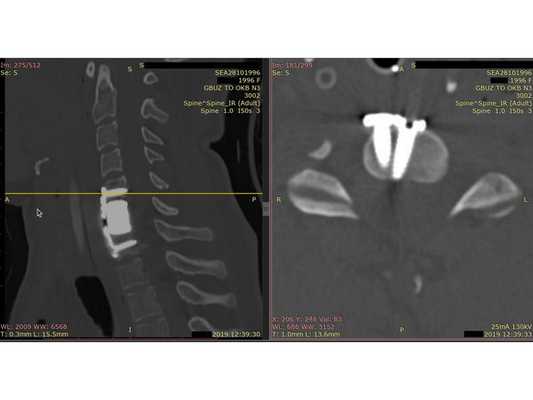

- Компьютерная томография шейного отдела позвоночника: выявлен компрессионно-оскольчатый перелом тела 6-го шейного позвонка (С6) и его дуги справа.

Контрольная КТ шейного отдела позвоночника на уровне тела позвонка С6. Виден установленный кейдж из пористого никелида титана и фиксирующая шейная пластина.